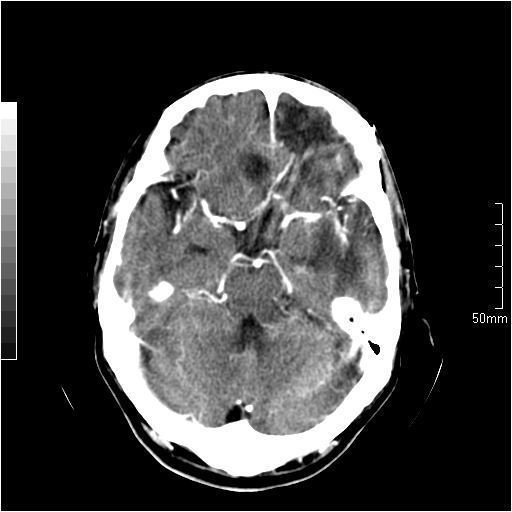

以下是引用天南地北在2007-6-25 12:39:00的发言:[br]有占位效应[br]支持术后复发

以下是引用zjzjr在2007-6-25 12:38:00的发言:[br]左侧复发,右侧转移。